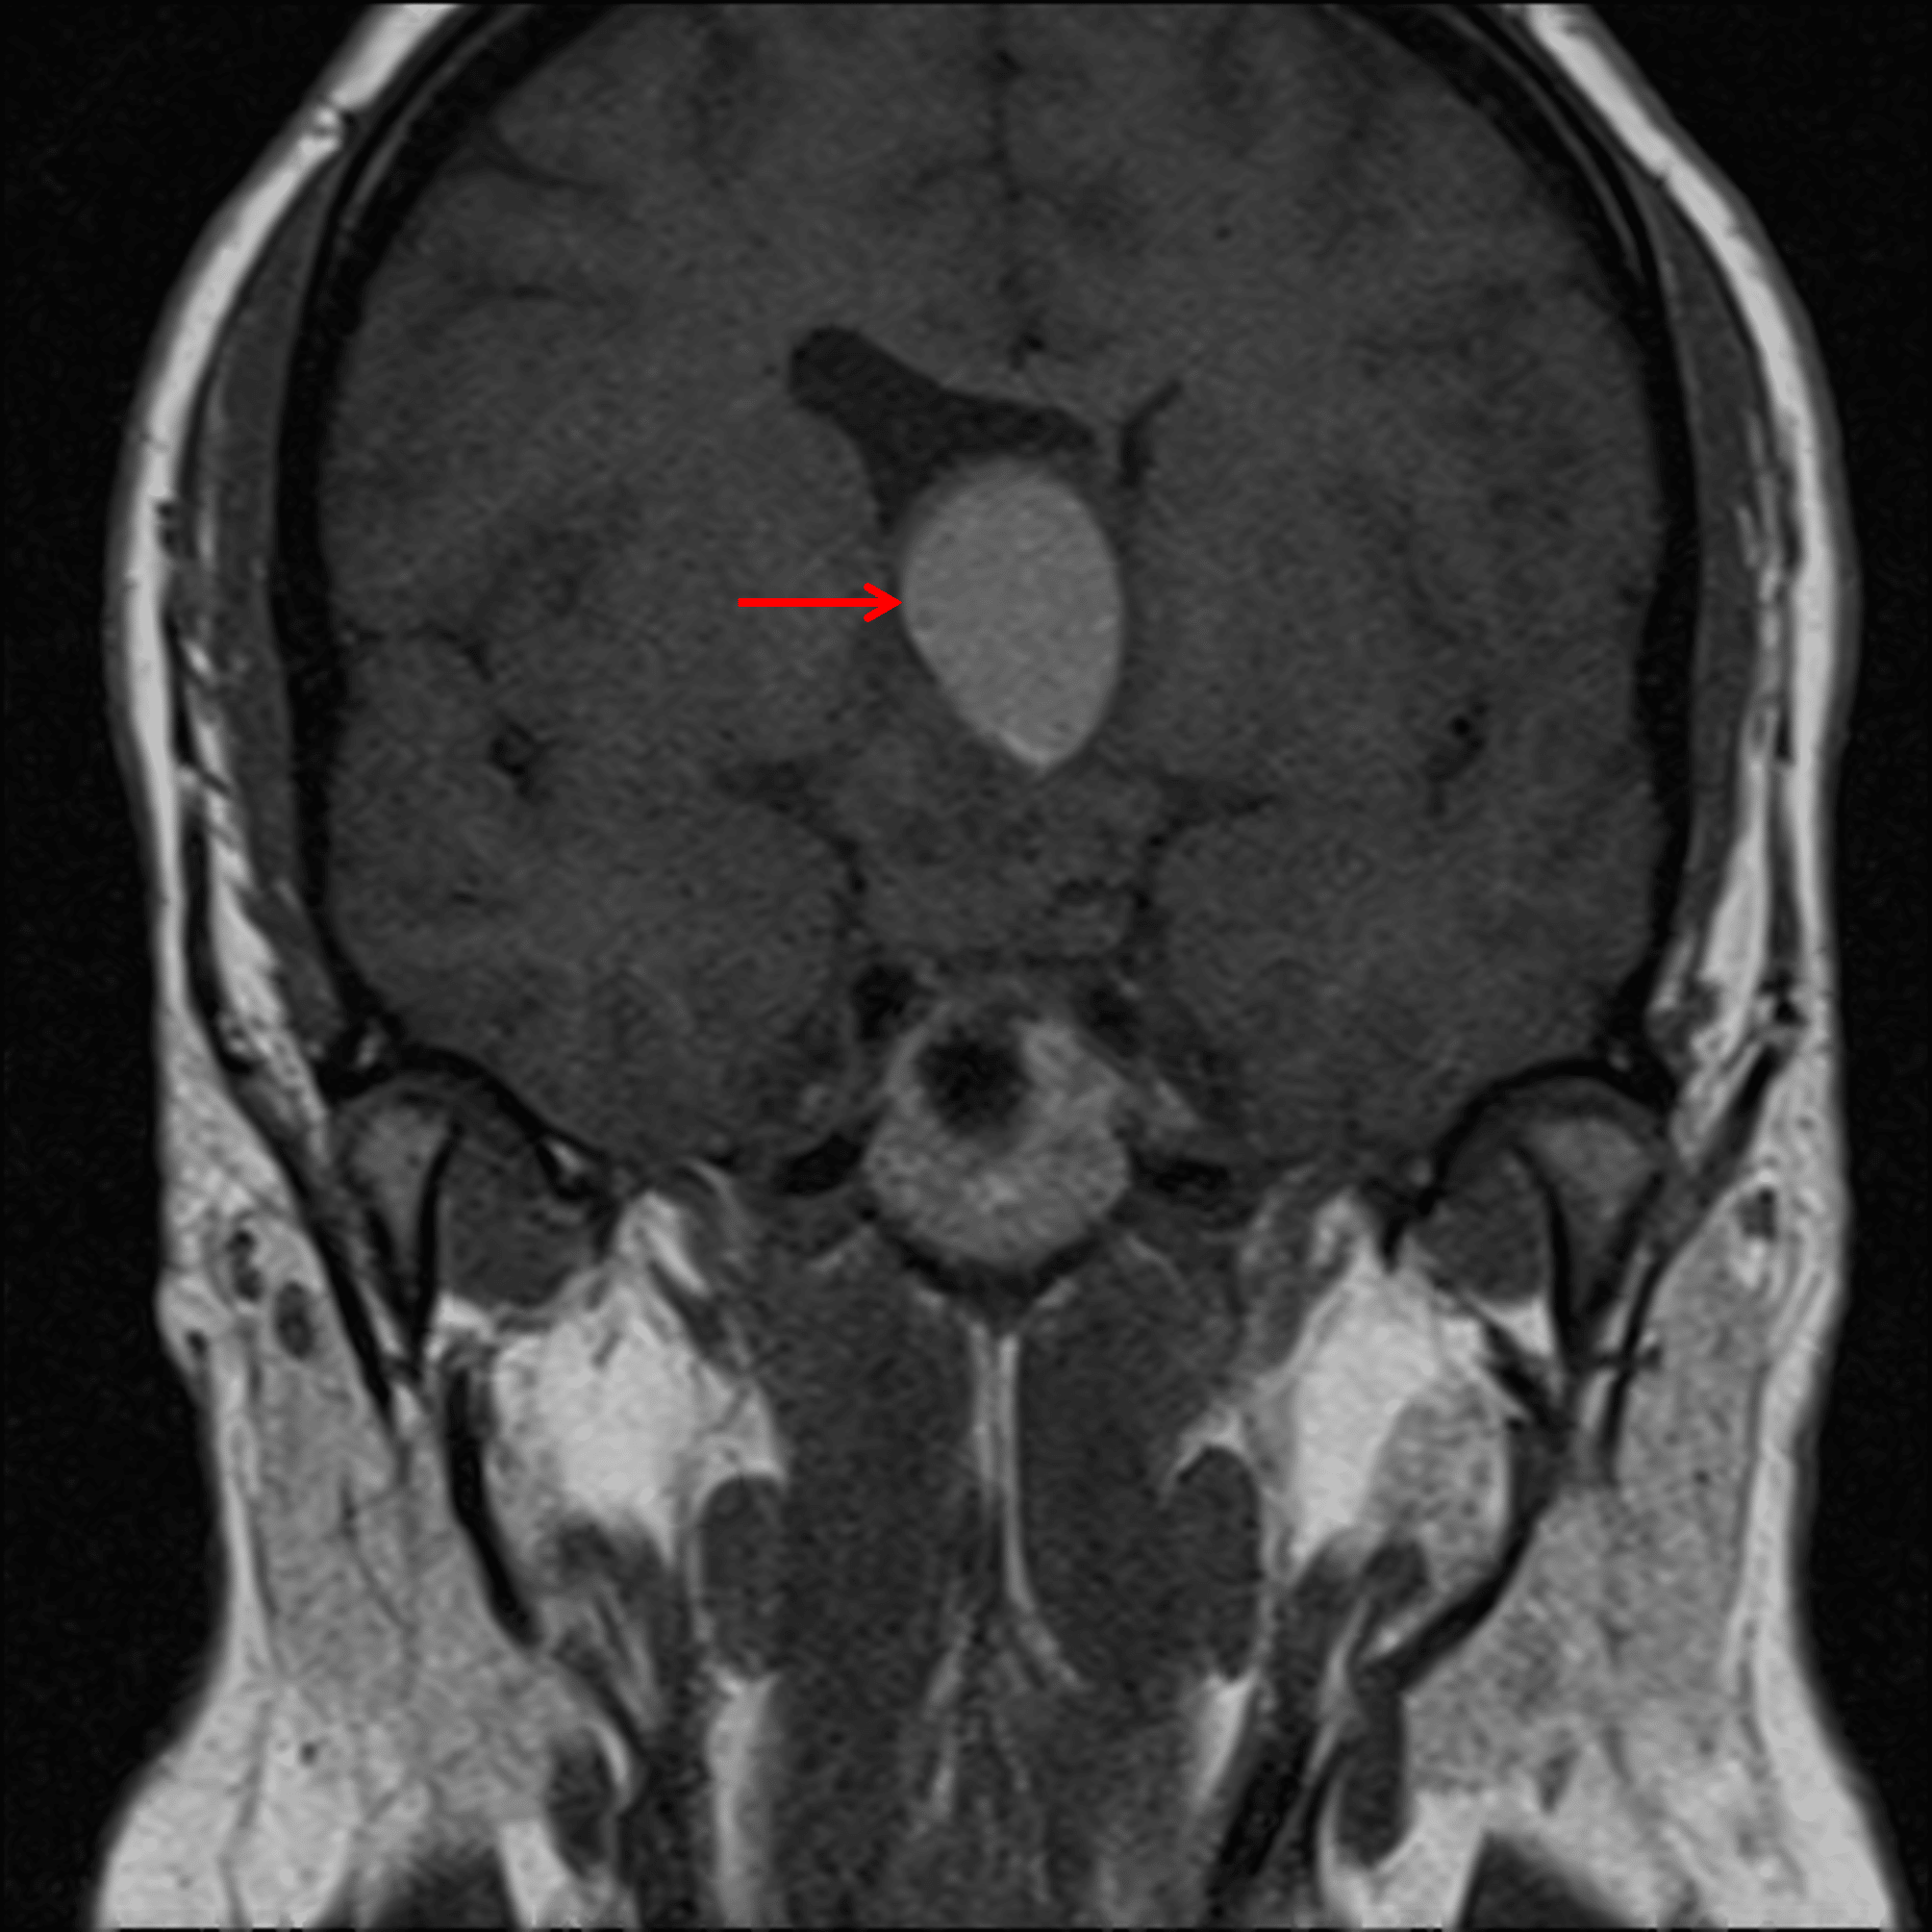

- Intrinsic T1 signal hyperintensity within a few of the cystic components (particularly the most anterosuperior cyst), which may represent intralesional hemorrhage or proteinaceous debris

Intrinsic T1 signal hyperintensity within one of the larger superior cysts (red arrow).